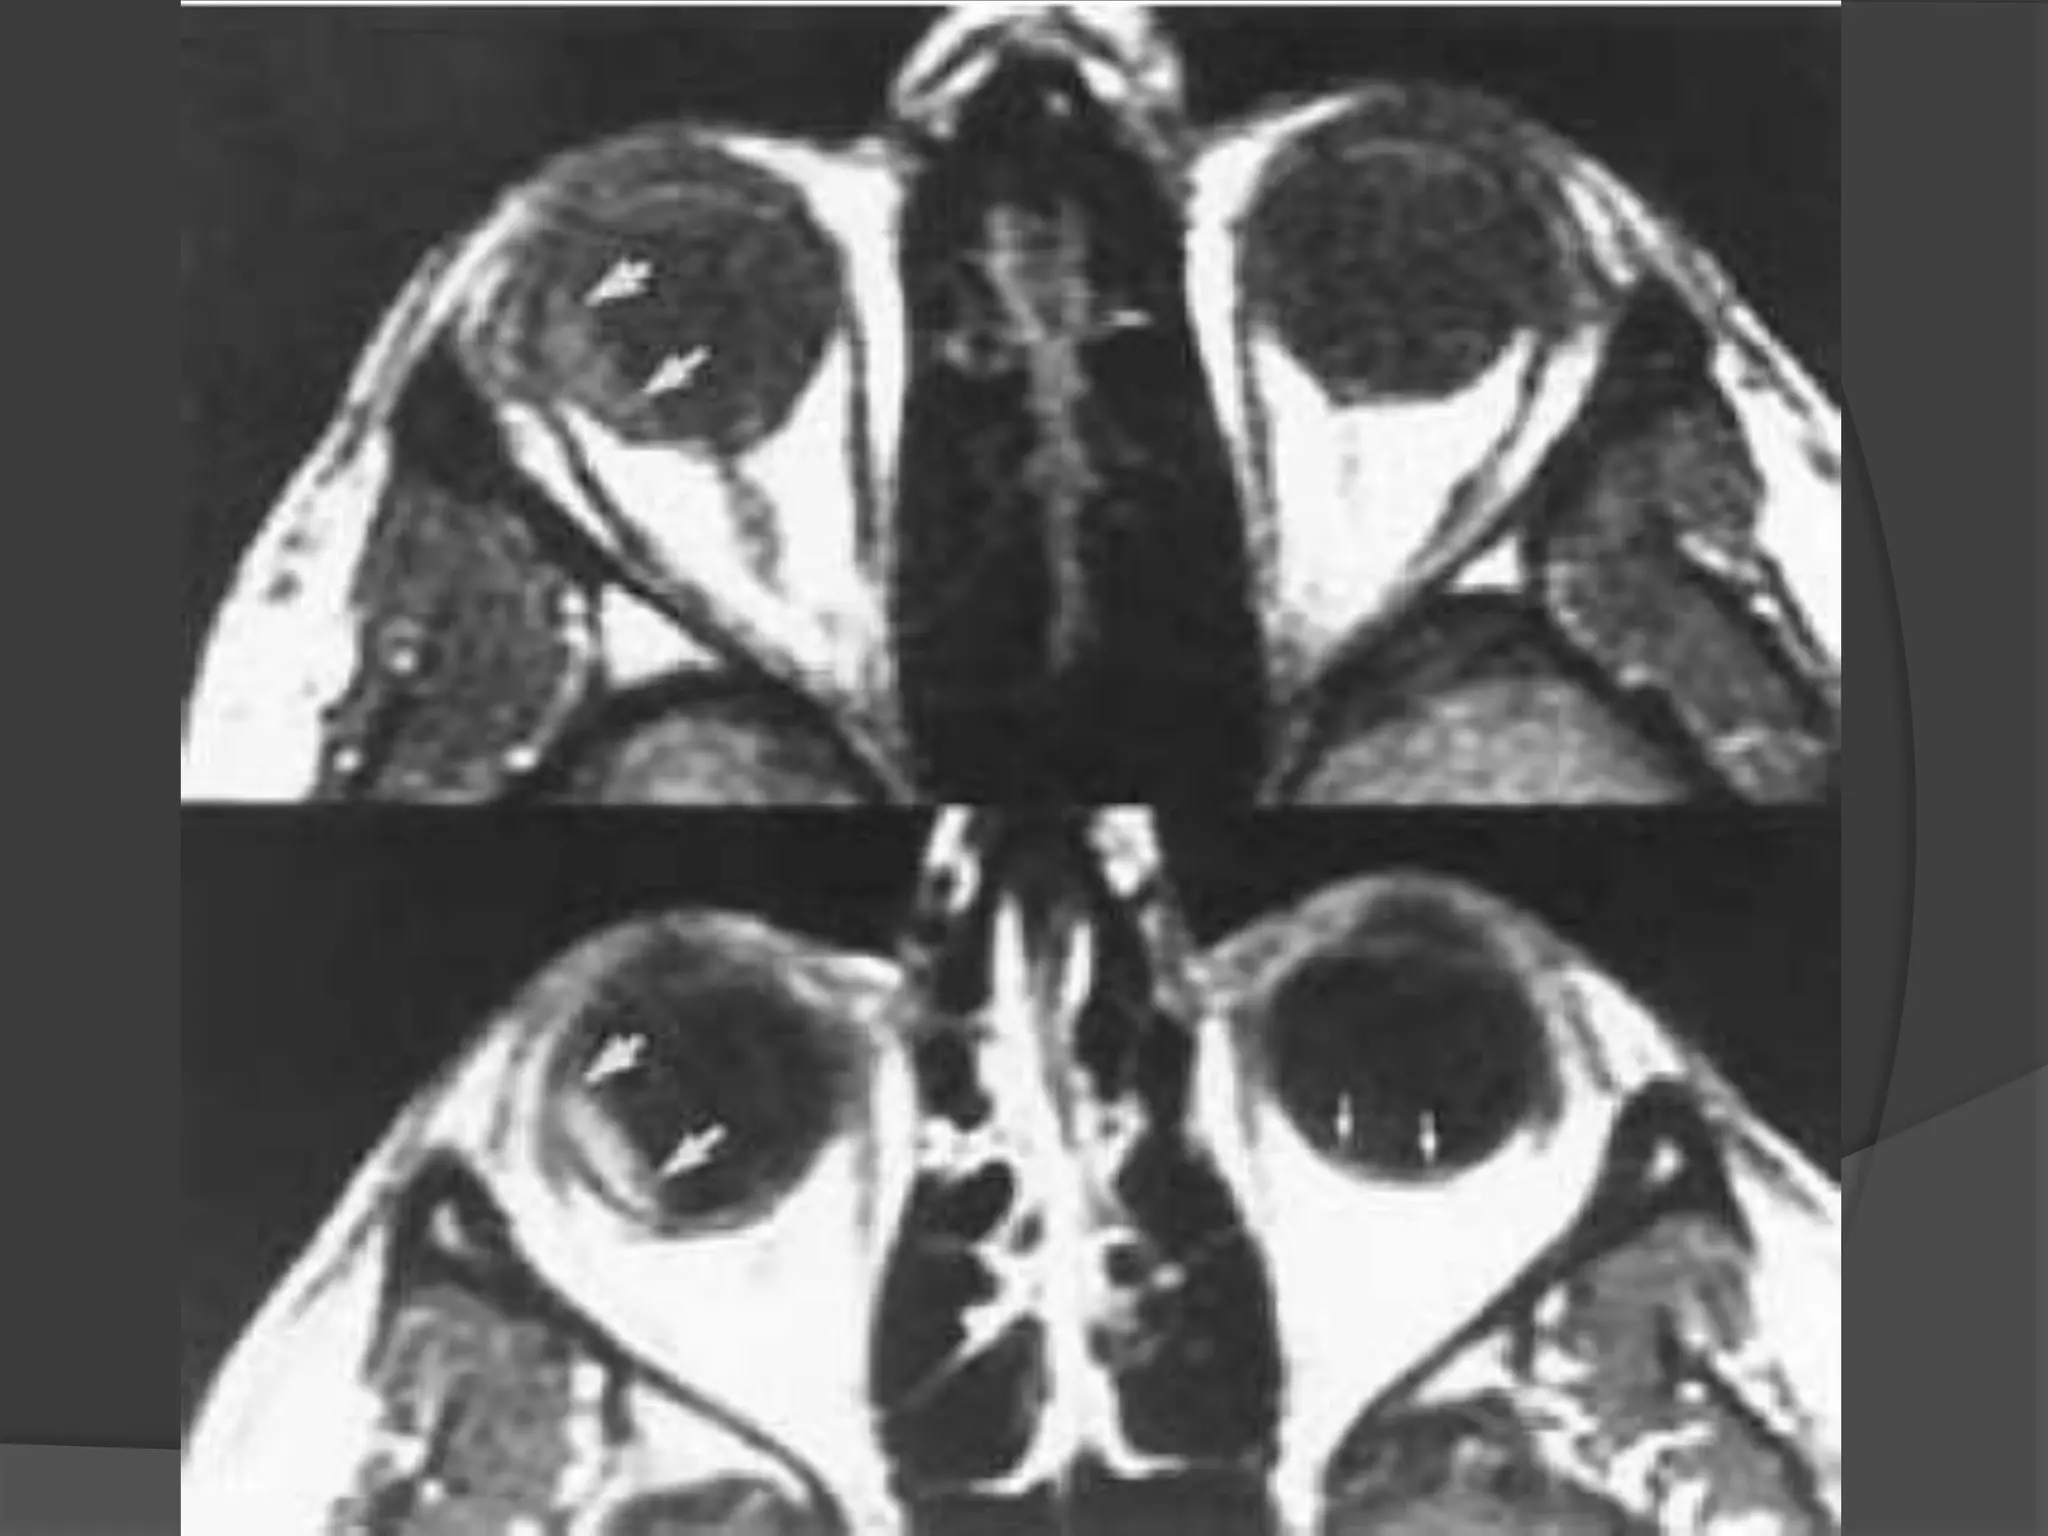

Imaging : MRI is the modality of choice with hyper intense signal of

T2WI due to fluid and edema. Fat Sat contrast enhanced T1WI will show

areas of demyelination. CT relatively insensitive.

Straightening and thickening

of right optic nerve.

Optic Neuritis. CE Fat Sat T1W axial

(B) MR images demonstrate subtle enlargement and enhancement of the left

optic nerve (curved arrow).

T 2 WI (C) demonstrates corresponding increased signal intensity (straight

arrow).